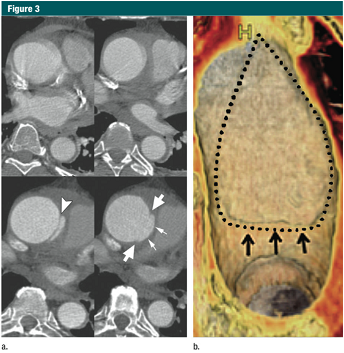

图3 升主动脉局限性内膜撕裂 (a)上方:无心电门控的CTA显示升主动脉运动伪影,模糊;下方:12小时后,心电门控 CTA示:升主动脉近端内膜皮瓣& #40;箭头& #41;,伴随一个侵蚀边缘的局限性内膜撕裂。局限性内膜撕裂的边缘(大箭头)和主动脉壁破坏形成的突起(小箭头)清晰可见。这些微妙细节如果没有使用心电门控是不可见的。 (b)VR重建显示腔内一侧150px长的损伤。一个小的破损皮瓣(细箭)代表撕裂的起始端,并一直延伸到主动脉弓的近端。虚线,代表撕裂的边缘。(转载,许可,引用24。)

少数有中层病变的患者,出现表浅或者部分撕裂(相当于原发性内膜撕裂),但并没有形成一个单独的流出道,或者造成壁内血液的存留。这些少见的病变称之为局限撕裂或者局限性夹层,与典型夹层对比往往具有细微的影像改变(30,33,36)(图3)。 In a smallnumber of patients with medial disease, a superficial/partial thickness tear develops & #40;the equivalent of a primary intimal tear& #41; without the development ofa separate flow channel or accumulation of intramural blood. These rare lesionsare referred to as limited tears or limited dissection and tend to have subtle imaging findings when compared with classic dissection & #40;30,33,36& #41;& #40;Fig 3& #41;.